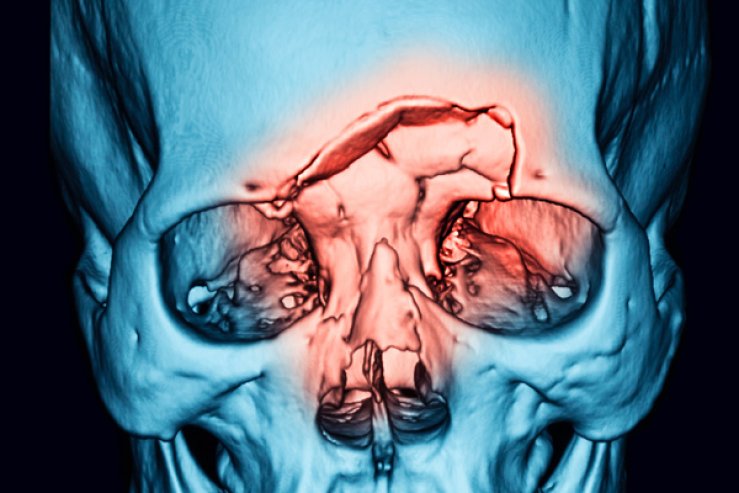

Щелепно-лицеві травми — одна з найчастіших причин госпіталізації. Це можуть бути переломи нижньої або верхньої щелепи, виличної дуги, носових кісток. У лікарні ім. І. І. Мечникова застосовуються найсучасніші методики фіксації — остеосинтез із використанням титанових пластин і гвинтів, що забезпечує точне зрощення кісток без порушення естетики обличчя. Пацієнти після таких операцій швидше повертаються до звичного життя, не потребують тривалого знерухомлення щелеп.

Онкопатологія щелепно-лицевої ділянки потребує комплексного підходу. У відділенні проводиться діагностика, біопсія та за показаннями — радикальне хірургічне видалення пухлин із подальшою реконструкцією.

Лікарі застосовують методи мікрохірургічної пластики для відновлення форми обличчя після видалення новоутворення, що допомагає мінімізувати косметичні наслідки.